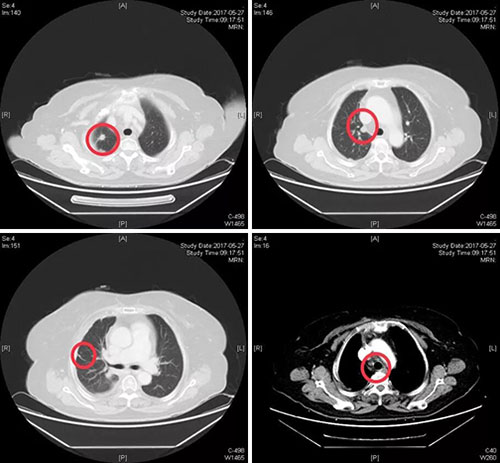

以下为影像学资料

2017年5月医院治疗前胸腹部强化CT:右肺上叶占位、右肺多发小结节、纵隔淋巴结肿大并增强扫描时强化。

胸腹部强化CT:右侧胸膜条状、结节状增厚并强化。提示胸膜转移。